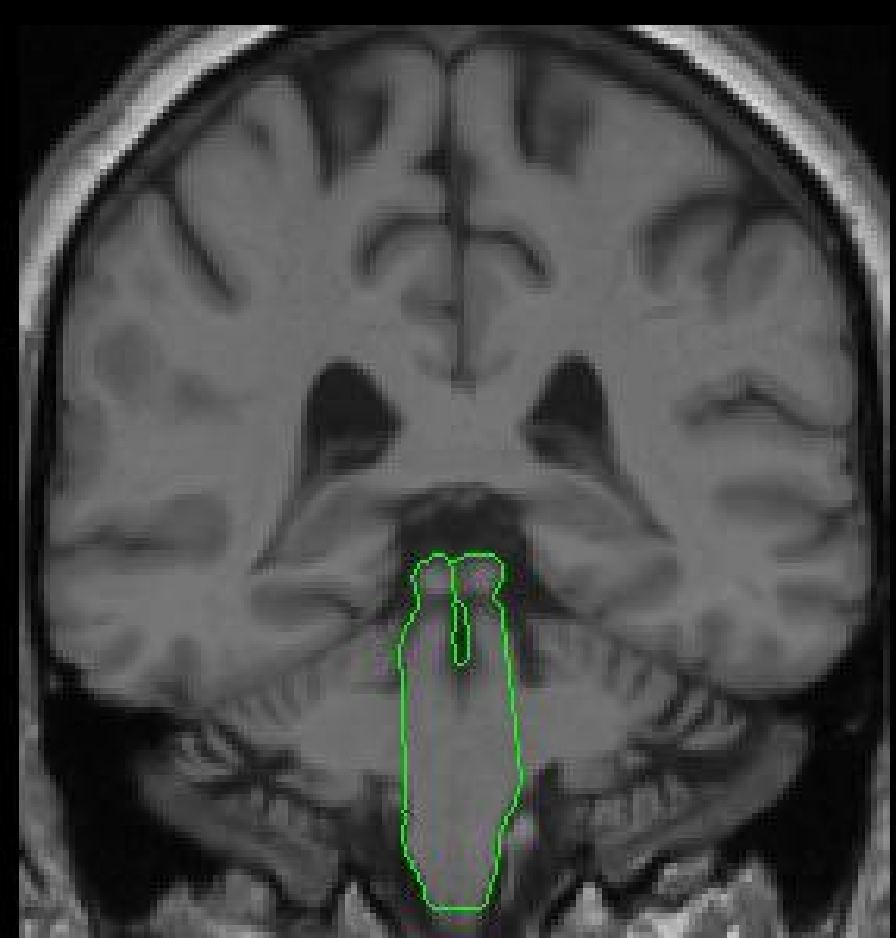

The three parts of the brainstem include the midbrain (mesencephelon), the

pons, and the medulla. The most superior part of the brainstem is the midbrain

which continues behind the pons and down to the medulla. The more anterior,

superior part of the brainstem is the pons and the more posterior, inferior

part of the brainstem is the medulla, although there is some overlap. The

pons is an apple shaped structure, which sits on the anterior side of the

more stalk-like medulla. The medulla leads directly into the spinal cord.

Part II - Anterior portion of the brainstem

1. Begin segmenting the brainstem when the first slice containing the brainstem is visible. Use the contour function (C) to create a contour that hugs the area of the brainstem. The draw function will also need to be used to connect parts of the contour that are not connected, or to exclude non-brainstem parts from the outline. It may be necessary to use the piece-wise contour method (V) on certain areas of the brainstem.